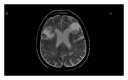

Opercular syndrome, also known as Foix-Chavany-Marie syndrome, is a paralysis of the facial, pharyngeal, masticatory, tongue, laryngeal, and brachial muscles. It is a rare cortical form of pseudobulbar palsies caused by vascular insults to bilateral operculum. Its clinical presentations include anarthria, weakness of voluntary muscles involving face, tongue, pharynx, larynx, and masticatory muscles. However, autonomic reflexes and emotional activities of these structures are preserved. In the present case, an 81-year-old male presented with acute onset of anarthria with difficulties in chewing, speaking, and swallowing that was diagnosed with opercular syndrome.